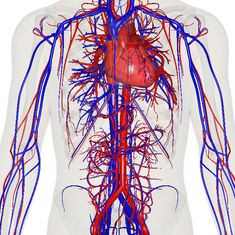

Depiction of the heart, major veins and arteries constructed from body scans

The essential components of the human cardiovascular system are the heart, blood and blood vessels.[6] It includes the pulmonary circulation, a "loop" through the lungs where blood is oxygenated; and the systemic circulation, a "loop" through the rest of the body to provide oxygenated blood. The systemic circulation can also be seen to function in two parts – a macrocirculation and a microcirculation. An average adult contains five to six quarts (roughly 4.7 to 5.7 liters) of blood, accounting for approximately 7% of their total body weight.[7] Blood consists of plasma, red blood cells, white blood cells, and platelets. Also, the digestive system works with the circulatory system to provide the nutrients the system needs to keep the heart pumping.[8]